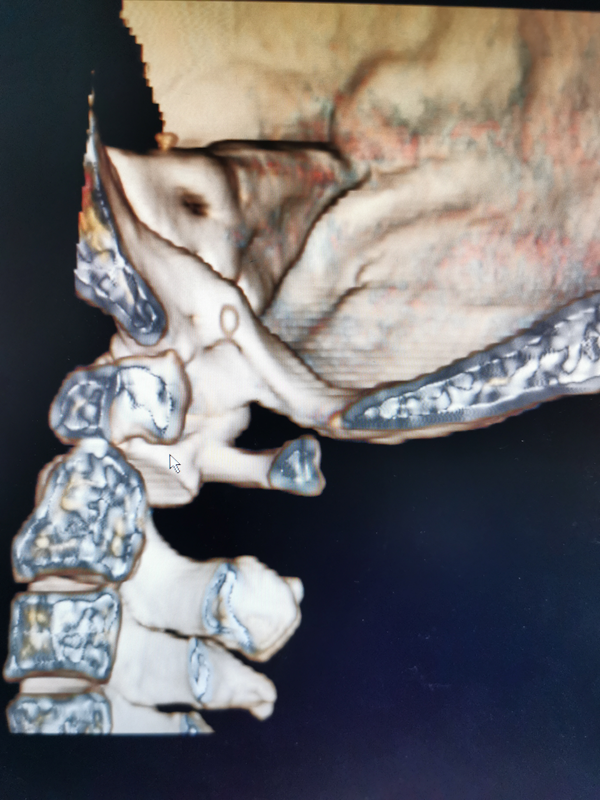

经过骨三科详细分析讨论后后,张纯主任医师、王伟卓副主任医师为患者精心设计了手术方案,术前3D打印制定了模板。1月10日,在麻醉科、手术室等医务人员的密切配合下,韩新生教授麻醉,张纯主任医师主刀、王伟卓副主任医师、曾思想、黄思华主治医师为患者实施手术。术中王芳为患者实时肌电监护。经过 3小时的精心操作和努力,成功为患者行了颈椎后路寰枢椎椎弓根螺钉内固定及寰枢植骨融合术,术中患者出血不到200ml,手术取得圆满成功。